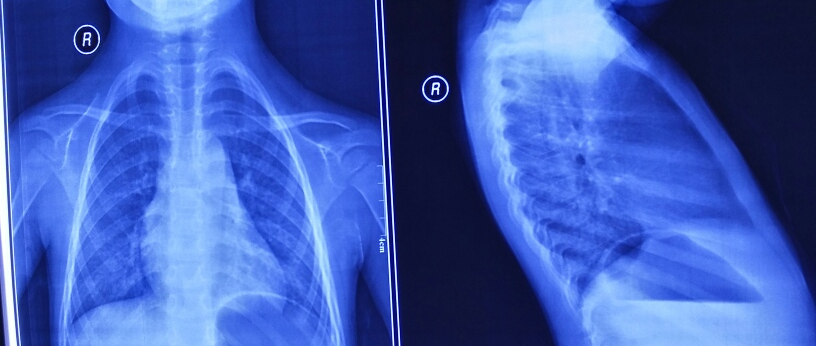

1.鸡胸、漏斗胸NUSS手术的优势:与胸骨翻转术、胸骨抬举术等治疗漏斗胸的传统手术相比,NUSS手术的优点为:1.创伤小(不切胸骨和肋骨);2.出血少(5-10ml);3.手术时间短(30-40分钟);4.术后恢复快,5.钢板固定稳固;6.前胸不切口,外形美观;7.效果显著。

4.小儿先天性心脏病的直视治疗

5.右侧腋下微创小切口治疗先心病

6.胸腔镜治疗动脉导管未闭